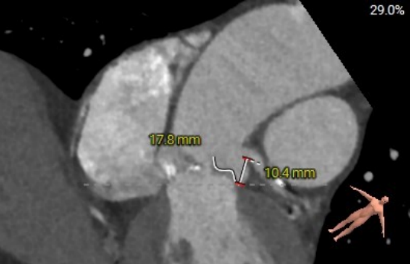

左冠瓣叶长度:17.8mm

右冠瓣叶长度:13.0mm

主动脉瓣环夹角:56°